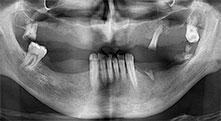

Брату: Ние използваме инструментите за събиране на костни блокове и разделяне на алвеоларни гребени. Ние също използваме Piezomed B6/B7 за остеотомия на наранени зъби и отстраняване на неуспешни импланти. Всички индикации, които изискват дълбоки, чисти разрези.

Брату: Ние предпочитаме да събираме кост от външната страна на гребена в задната част на долната челюст. След разрязване на меките тъкани, ние използваме новите триони, за да определим количеството кост, което ще събираме. С този подход, ние използваме трионите за цялата препарация в почти 80% от случаите. Може да използваме и други пиезо инструменти и накрая длето за мобилизиране на блока. Ние смятаме, че това е изключително ефективна хирургична техника.

Брату: Ние предпочитаме да използваме техниката "сандвич" за аугментация в страничната долна челюст. Покритие на костта се подготвя с пиезо трион и кресталният фрагмент се фиксира с микровинтове. Поставяме смес от автогенна костна присадка и ксеногенен костозаместител между тях. Това работи много надеждно. Трябва винаги да осигурявате достатъчно оразмерени вертикални срезове при шиниране на алвеоларния гребен в долната челюст. В противен случай, костта лесно може да бъде счупена.

Брату: Смятам, че пиезохирургията е огромна крачка напред в оралната хирургия. Тази техника прави препарацията на кост много по-безопасна и по-лесна. Загубата на кост е малка, например при екстракции. Това е много важно в естетичната зона, особено ако е планирано имедиатно имплантиране. Пиезохирургията е по-безопасна за меките тъкани: нараняването на мембраната в синуса е вече в историята, както и засягането на нервите при събиране на костни блокове. Данните сочат намалено постоперативно подуване и болка. Пиезохирургията също е перфектна за препарация на синусните прегради. И накрая, но не на последно място, нашите пациенти се радват на атравматичния характер на тази технология.